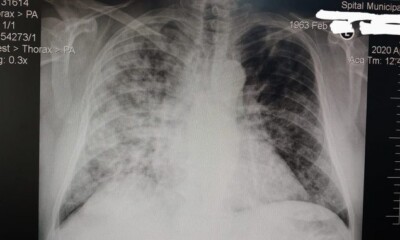

Un medic din Alba a prezentat sâmbătă seara radiografia unui pacient infectat cu COVID-19, care a fost internat și tratat la Spitalul suport din Blaj. Potrivit...